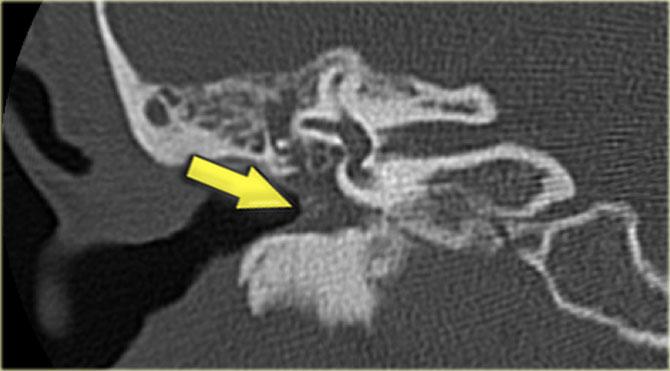

Viêm mê đạo xương hóa (Labyrinthitis ossificans)

Viêm mê đạo xương hóa thường gặp sau viêm màng não.

Đây là tình trạng tai trong bị lấp đầy bởi mô xơ, sau đó tiến triển thành vôi hóa.

Tổn thương chủ yếu ảnh hưởng đến ốc tai, tuy nhiên tiền đình và các ống bán khuyên cũng có thể bị liên quan.

Hình ảnh bên trái của bệnh nhân nam 56 tuổi, là ứng viên cấy ốc tai điện tử.

Vôi hóa nhỏ tại vòng đáy ốc tai là hậu quả của viêm mê đạo xương hóa (mũi tên).

Hình ảnh bên trái của bệnh nhân nam 14 tuổi với điếc tiếp nhận hai bên.

Vôi hóa ống bán khuyên trên bên trái (mũi tên vàng).

Tai phải để so sánh (mũi tên xanh lam).

Hình ảnh mặt phẳng coronal của cùng bệnh nhân trên.